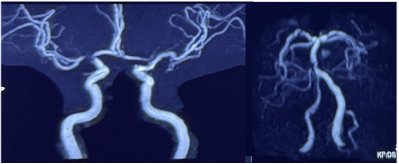

头颅MRA:椎动脉(R-VA)、基底动脉(BA)、右大脑中动脉(R-MCA)、右大脑后动脉(R-PCA)多发节段性重度狭窄(图4)。

image.png

图4 头颅MRA